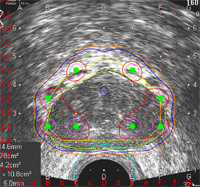

Prostate Brachytherapy

The Seattle Prostate Institute (SPI)pioneered the use of prostate brachytherapy – the technique of delivering radiation 'seeds' to the prostate under ultrasound guidance. The institute was established in 1997 by our physicians who had developed this technology in the mid 1980s here in Seattle. SPI physicians have performed more than 10,000 prostate implants. Almost half of these patients have come from other states and countries in order to benefit from our expertise. Prostate brachytherapy has taken off as a preferred method of treating low-risk prostate cancer, in part due to the robust long term data that we have published showing high cure rates and low toxicity. Physicians, residents, and other health professionals attend the Seattle Prostate Institute educational courses and our annual conference. SPI physicians have maintained their leadership role through these lectures, our research, and by providing ongoing assistance to physicians around the country with our remote dosimetry services. The Seattle Prostate Institute is the prostate cancer 'arm' of TIROG.